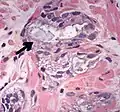

Intraductal carcinoma of the prostate with an infiltrative growth pattern may be morphologically difficult to distinguish from invasive cancer. One focus shows comedonecrosis (arrow), morphologically suggesting Gleason pattern 5 invasive carcinoma (a haematoxylin and eosin, b CK5/6)[19]